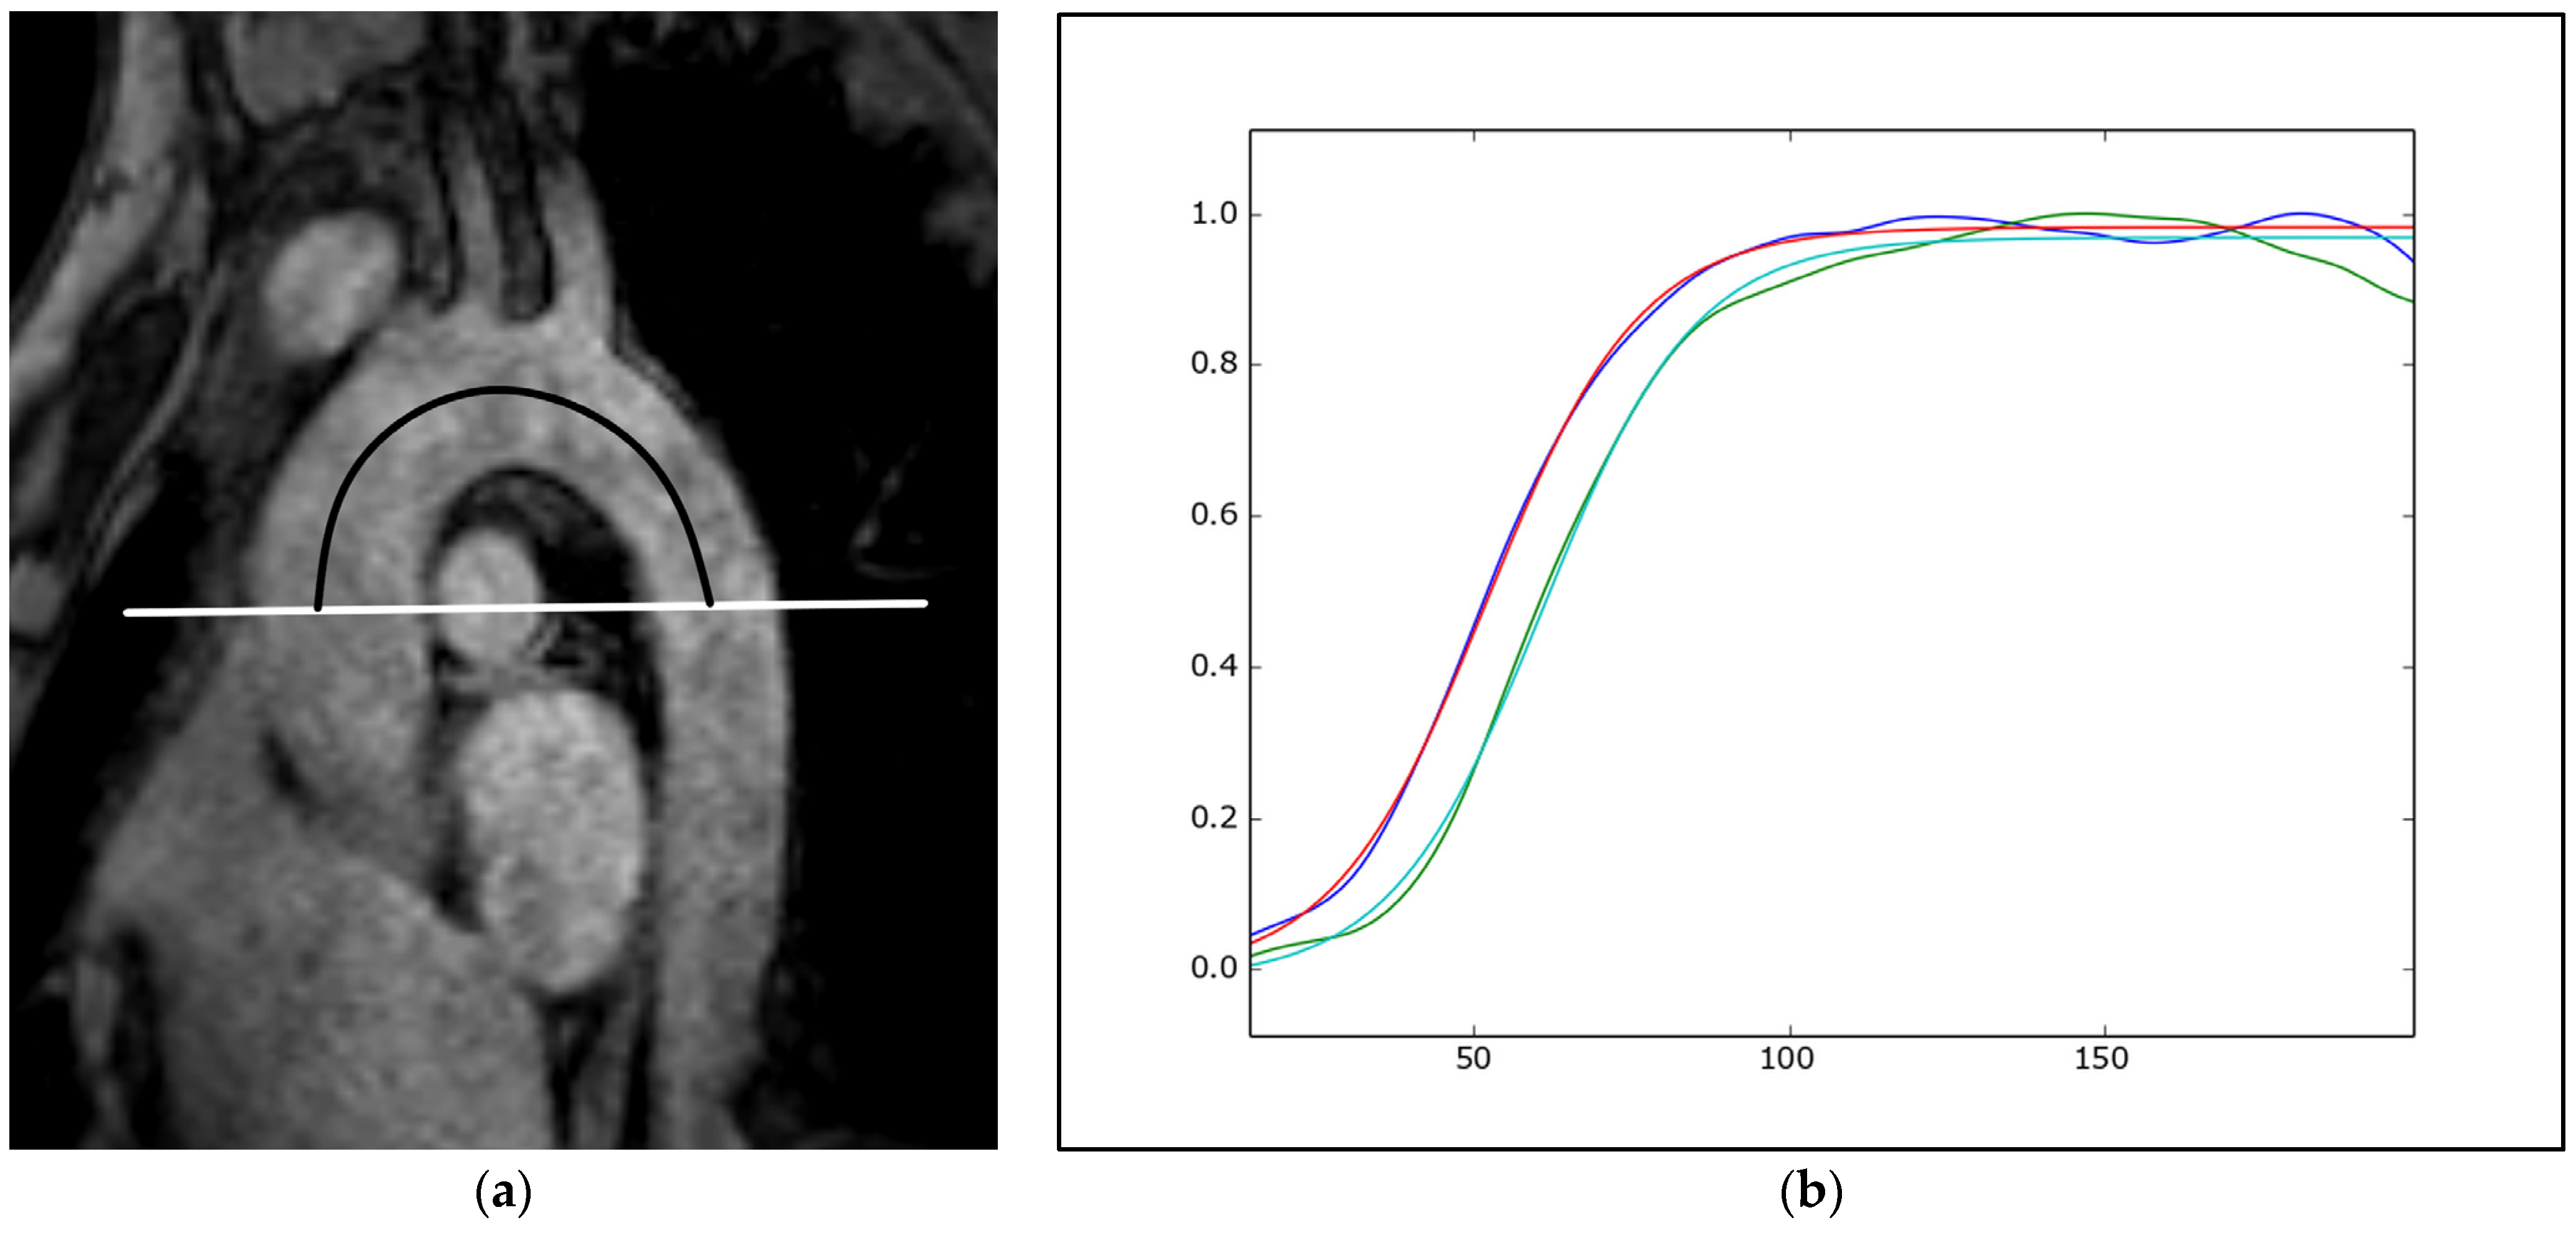

5.3. Magnetic Resonance Imaging

- Parikh, J.D.; Hollingsworth, K.G.; Kunadian, V.; Blamire, A.; MacGowan, G.A. Measurement of pulse wave velocity in normal ageing: Comparison of Vicorder and magnetic resonance phase contrast imaging. BMC Cardiovasc. Disord. 2016, 16, 50. [Google Scholar] [CrossRef]

- Dogui, A.; Redheuil, A.; Lefort, M.; DeCesare, A.; Kachenoura, N.; Herment, A.; Mousseaux, E. Measurement of aortic arch pulse wave velocity in cardiovascular MR: Comparison of transit time estimators and description of a new approach. J. Magn. Reson. Imaging 2011, 33, 1321–1329. [Google Scholar] [CrossRef]

- Soulat, G.; Gencer, U.; Kachenoura, N.; Villemain, O.; Messas, E.; Boutouyrie, P.; Laurent, S.; Mousseaux, E. Changes in segmental pulse wave velocity of the thoracic aorta with age and left ventricular remodelling. An MRI 4D flow study. J. Hypertens. 2020, 38, 118–126. [Google Scholar] [CrossRef]

- Loose, S.; Solou, D.; Strecker, C.; Hennemuth, A.; Hüllebrand, M.; Grundmann, S.; Asmussen, A.; Treppner, M.; Urbach, H.; Harloff, A. Characterization of aortic aging using 3D multi-parametric MRI-long-term follow-up in a population study. Sci. Rep. 2023, 13, 6285. [Google Scholar] [CrossRef] [PubMed]

- Redheuil, A.; Kachenoura, N.; Bollache, E.; Yu, W.C.; Opdahl, A.; Decesare, A.; Mousseaux, E.; Bluemke, D.; Lima, J.A.C. Left ventricular and proximal aorta coupling in magnetic resonance imaging: Aging together? Am. J. Physiol. Heart Circ. Physiol. 2019, 317, H300–H307. [Google Scholar] [CrossRef]

- Hrabak-Paar, M.; Kircher, A.; Al Sayari, S.; Kopp, S.; Santini, F.; Schmieder, R.E.; Kachenoura, N.; Yates, D.; Langenickel, T.; Bremerich, J.; et al. Variability of MRI Aortic Stiffness Measurements in a Multicenter Clinical Trial Setting: Intraobserver, Interobserver, and Intracenter Variability of Pulse Wave Velocity and Aortic Strain Measurement. Radiol. Cardiothorac. Imaging 2020, 2, e190090. [Google Scholar] [CrossRef]

- Herment, A.; Kachenoura, N.; Lefort, M.; Bensalah, M.; Dogui, A.; Frouin, F.; Mousseaux, E.; De Cesare, A. Automated segmentation of the aorta from phase contrast MR images: Validation against expert tracing in healthy volunteers and in patients with a dilated aorta. J. Magn. Reson. Imaging 2010, 31, 881–888. [Google Scholar] [CrossRef]

| Magnetic resonance imaging | Cardiac morphology and function Aortic morphology and stiffness (pulse wave velocity, aortic strain, and distensibility) | Imaging modality of choice for advanced assessment of cardiac morphology and function Non-invasive myocardial ischemia testing (stress test) Commonly used for follow-up of aortic diseases (especially in children and younger individuals) | Non-invasive myocardial tissue characterization Image acquisition in any desired plane The gold standard for assessment of myocardial mass, ventricular volumes, and ejection fraction | High costs Limited availability Long-lasting examinations Contraindications (ferromagnetic foreign bodies, non-conditional cardiac implantable electronic devices) |